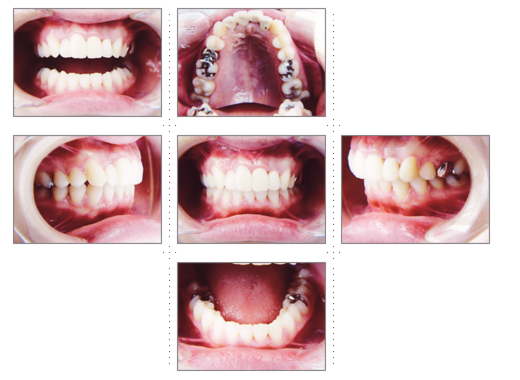

症例1

理学療法士 36才 女性

上下の歯並びを直したいというご希望で、来院。

術前と術後では、歯並び表情が変わった事はもちろんのこと、顔の形も変わり、「美容整形をしたように小顔になれました」と喜んでいただけました。